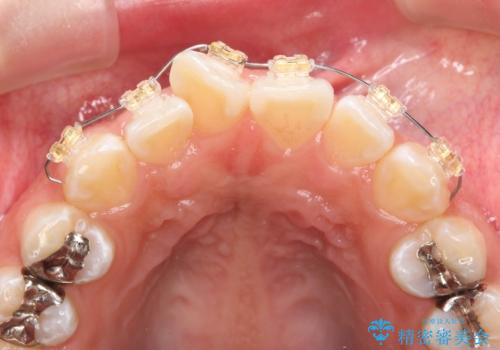

- 前歯の目立つねじれを矯正治療で治したい、と来院されました。

マウスピース矯正を始める前に、ねじれを取るのが短期間で済む部分ワイヤー小矯正を行うことで、全体的な治療期間を短くする治療計画を実行していきます。

前歯のねじれはマウスピース矯正の苦手な動きになり、治療期間が長くなる原因になりやすいです。